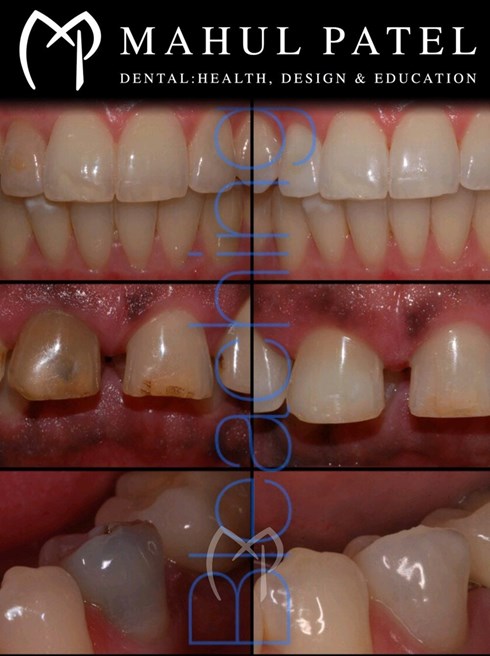

• Provision of full mouth reconstruction (fixed, removable and implant)